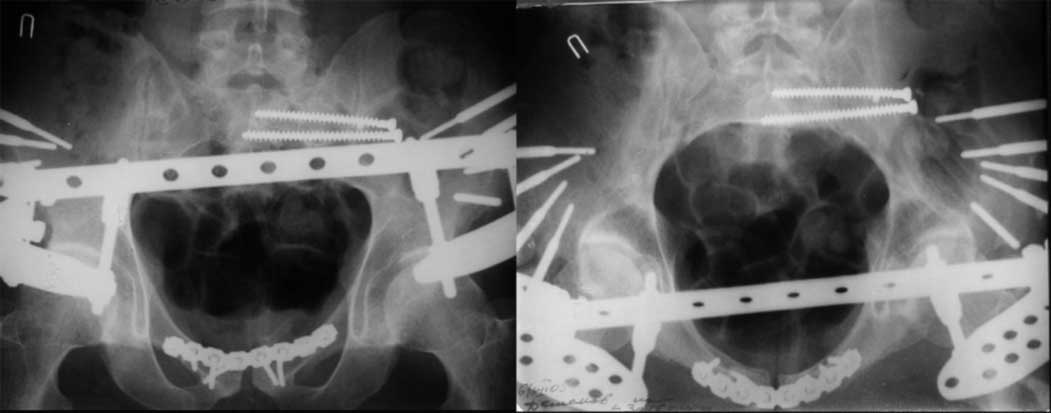

закрытое низведение правой половины таза кольцевым аппаратом (с фиксацией задних отделов), затем проведение илиосакральных винтов, реостеосинтез лонного сочленнения, дальнейшая фиксация в аппрате 2-3 мес. Похожий пример в приложении.

Дорогой Андрей. Мы имеем дело с комбинированной (ротационно и вертикально) нестабильностью таза со смещением правого гнемипелвиса. При таких переломах, фиксация только переднего полукольца вне зависимости от метода фиксации, как уже было сказано Djoldas Kuldjanov, M.D., не может создать адекватной фиксации. И перелом пластины был вполне ожидаемым после активизации пациента. Смещение сохраняется, и по-видимому не 2 см., а все 4, если не более. Разница всего (+2 см) по конечностям как вы указываете, скорее скомпенсировано позвоночником и протезом. Дополнительные снимки или КТ исследование помогли бы уточнить степень смещения с точностью до мм., выявить перелом поперечного отростка пятого поясничного позвонка, или помимо разрыва правого крестцово-подвздошного сочленения выявить перелом боковой массы крестца справа и т.д. При возможности, конечно, все это желательно сделать. Но мало что изменится с практической точки зрения, т.к. задача - это низведение репозиция и надежная фиксация правого гемипелвиса. Учитывая плачевный опыт стержневого аппарата, давность травмы совершенно очевидно, что поставленная задача достижима при открытой репозиции и одномоментной фиксации переднего полукольца с артродезированием правого крестцово-подвздошного сустава. Операция выполняется в положении больного на здоровом боку или полубоку из расширенного трансоссального подвздошно-пахового доступа с переходом на лонное сочленение доступом по Pfannenstiel. Указанный доступ обеспечивает подход к крестцово-подвздошному сочленению как спереди так и сзади. После артродезирования выполняется синтез лонного сочленения. Клинический пример

Пациентка С.26 лет. Травма за 6 месяцев до поступления

Укорочение правой нижней конечности до 10см

23.09.2003. Одновременный остеосинтез переднего и заднего тазовых полуколец

Результат через 10 дней

и 8месяцев после операции